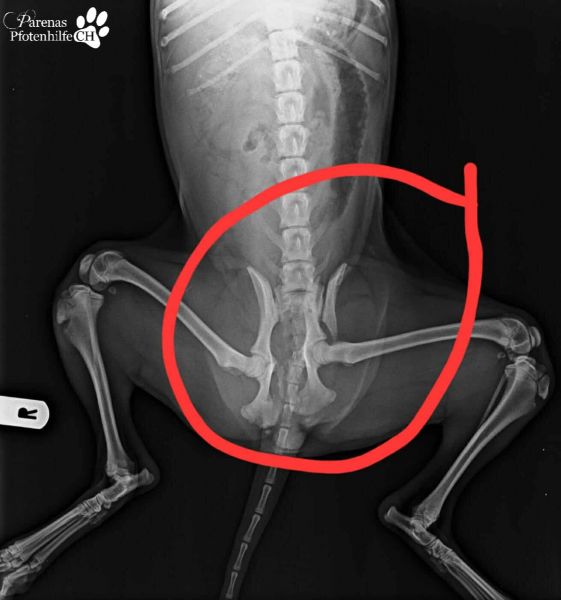

Das Leben für diesen Engel ist noch voller Schmerz und Angst. Von einem Auto angefahren, wurde die Maus in der Perrera Cordoba abgegeben. Sie hat diesen Unfall schwer verletzt überlebt, und jetzt beginnt für sie ein neues Kapitel.

Virginia brachte sie direkt zu Joaquin, um erste Untersuchungen zu machen. Leider ist die Hüfte kaputt, was unsägliche Schmerzen verursacht. Morgen wird der kleine Schatz ebenfalls Luis, unserem Traumatologen, vorgestellt, damit abgeklärt werden kann, welche Möglichkeiten es gibt, dem Engel eine beschwerdefreie Zukunft zu schenken.